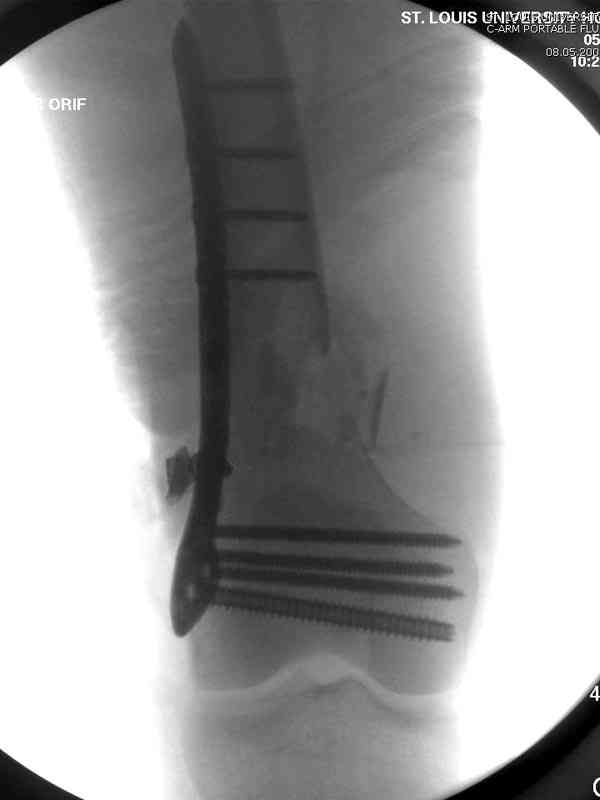

Больная К. с тугим ложным суставом н/3 бедра. Травма в 2005 г.-закрытый перелом, остеосинтез в аппарате Илизарова. В 2006 г. оперирована по поводу несросшегося перелома.

В ноябре 2006 г. демонтаж аппарата, после чего в течении месяца развилась вальгусная деформация. Имеется патологическая подвижность. Объем движений в коленном суставе 180-140. На обсуждение выносятся варианты лечения погружными конструкциями.

The patient with non-union of the distal femur. Trauma in 2005 - closed fracture of the femur, external fixation with Ilizarov apparatus. Non-union. In 2006 open reduction and external fixation with Ilizarov apparatus. In November 2006 the apparatus was removed, after that valgus deformation developed. There is pathological mobility. The knee motion 180-140. We'd like to discuss options of internal fixation.